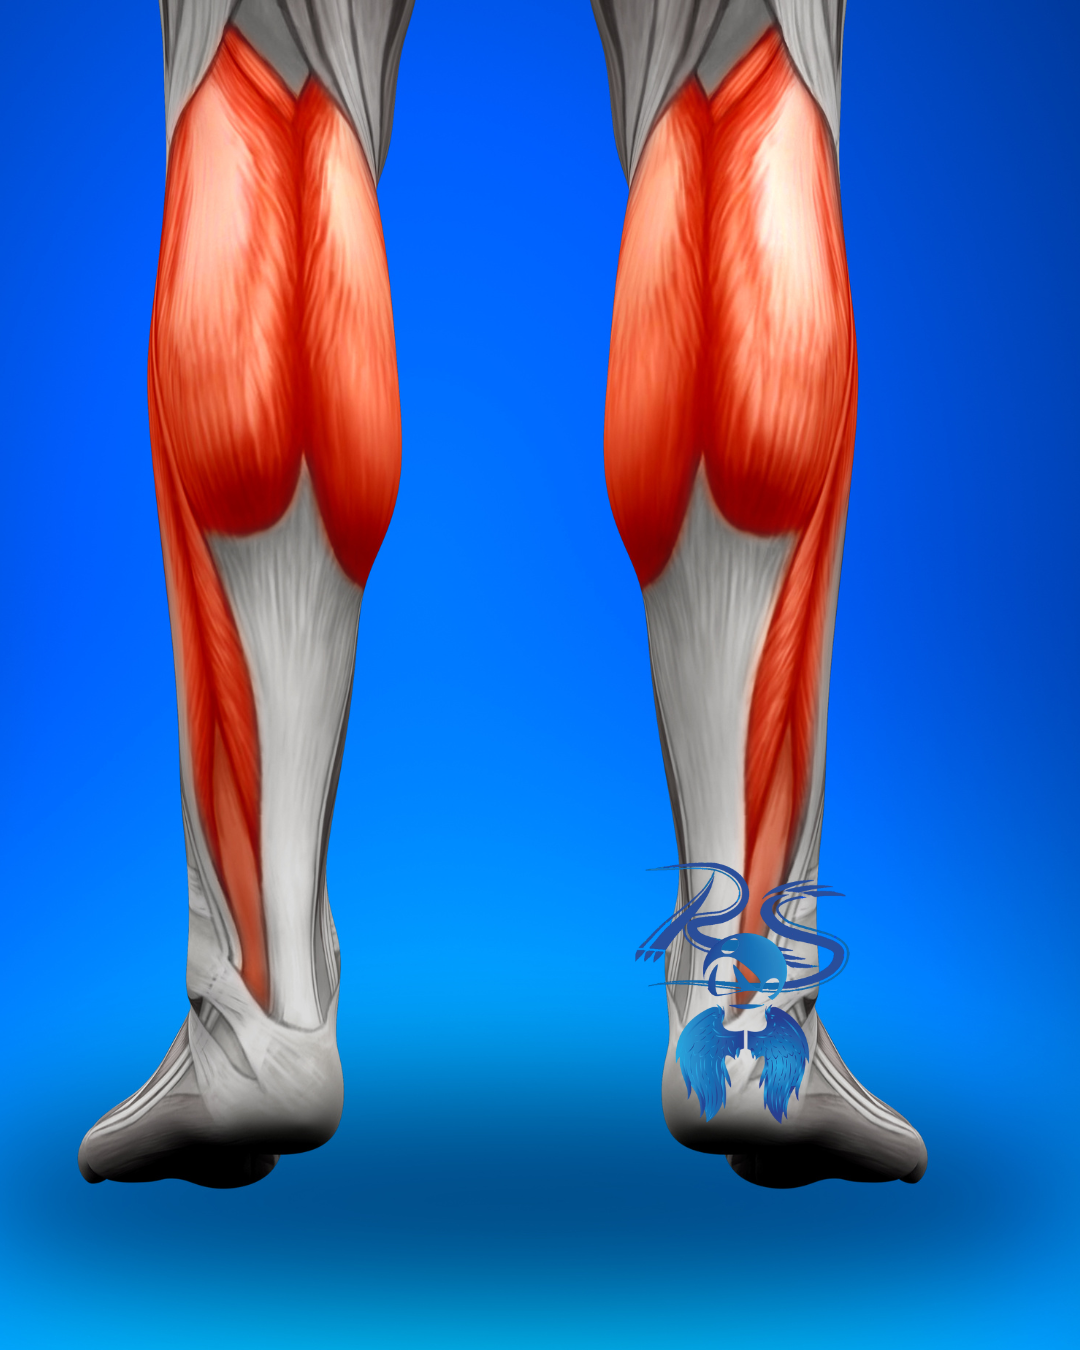

Pantorrillas: dolor que asciende

La tensión del pie suele reflejarse en gastrocnemio y sóleo.

Dolor que llega a rodillas

Cómo ayuda el masaje terapéutico: El masaje profundo mejora el retorno venoso y alivia la fatiga muscular.